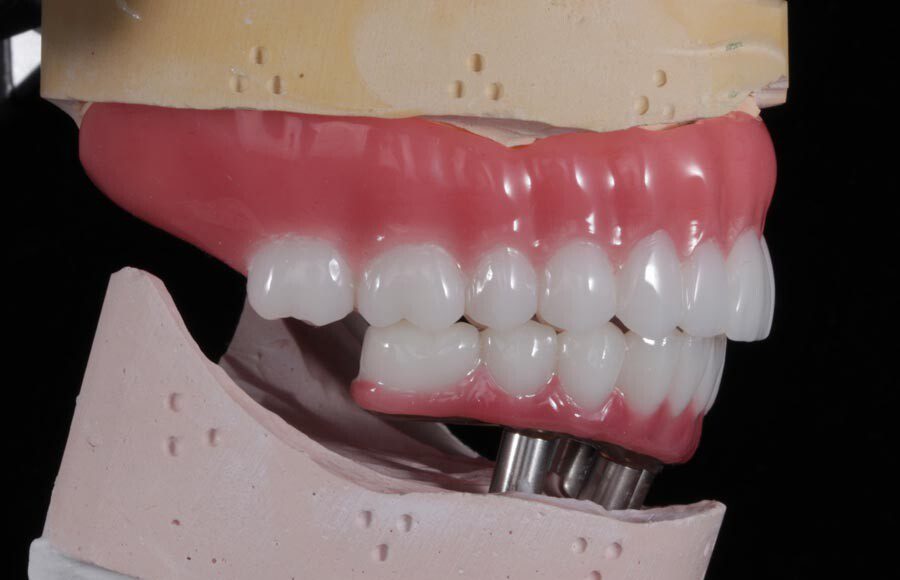

Smile GalleryImplant RestorationsImplant Dentures Post-op smiling 1 of 32 Pre-op close up smiling Pre-op lips retracted smiling Pre-op panoramic x-ray Implants in upper jaw (occlusal view) Implants in lower jaw (occlusal view) Panoramic x-ray of implants First set of try-ins – upper denture First set of try-ins – lower fixed provisional Delivered try-ins (lips retracted) Close adaptation to gums and appropriate emergence profile of lower fixed provisional Gum tissues have been molded by a convex provisional Delivered try-ins Second set of try-ins (lips retracted) Close adaptation to gums and appropriate emergence profile of second set of lower fixed provisional Delivered second try-ins Definitive restorations on casts (frontal view) Definitive restorations on cast (right side) Definitive restorations on cast (left side) Definitive upper overdenture (occlusal view) Definitive lower fixed titanium-acrylic hybrid restoration (occlusal view) Definitive lower fixed titanium-acrylic hybrid restoration (frontal view) Definitive lower fixed titanium-acrylic hybrid restoration (tissue side view) Healthy molded gum tissues on lower prior to delivery of lower fixed hybrid restoration Healthy gum tissues on upper prior to delivery of upper overdenture Definitive restorations (frontal, lips retracted) Definitive lower restoration (frontal) Definitive restorations (right side) Definitive restorations (left side) Definitive lower restoration (occlusal view) Definitive upper restoration (occlusal view) Post-op panoramic x-ray Post-op smiling